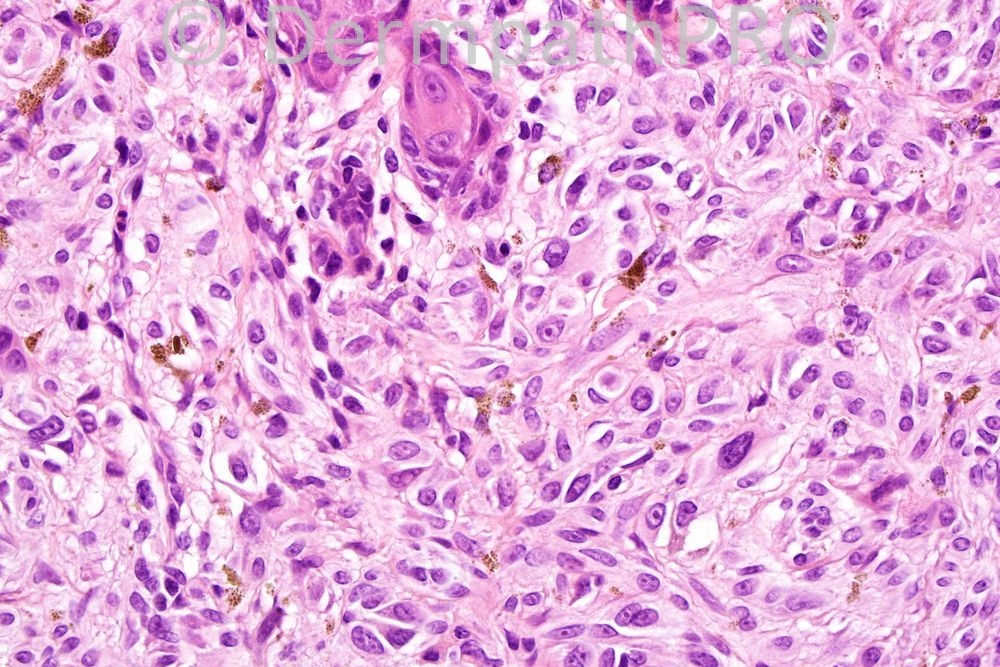

Male 11 years, lesion lower lip, increase in size.